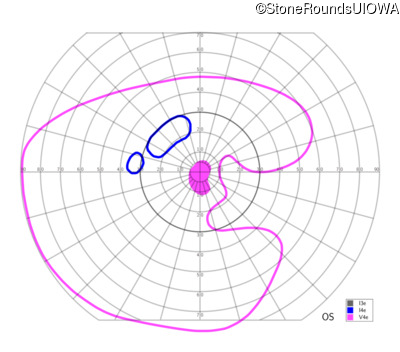

This 81 year old man began using a flashlight to read menus in his 40's. At age 75 his ophthalmologist noticed abnormal fundus findings and referred him to a retina specialist.

Diagnosis & molecular findings

| Late Onset Retinal Dystrophy | C1QTNF5 | Ser163Arg AGC>AGA | AD |